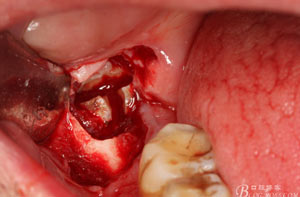

圖1。術(shù)前檢查的口內(nèi)像:48區(qū)域的位置有一瘺口。捫診溢膿。48未萌出。

圖6.行角形瓣切開(kāi)、翻瓣、暴露骨面,可見(jiàn)48牙冠表面有炎性肉芽組織